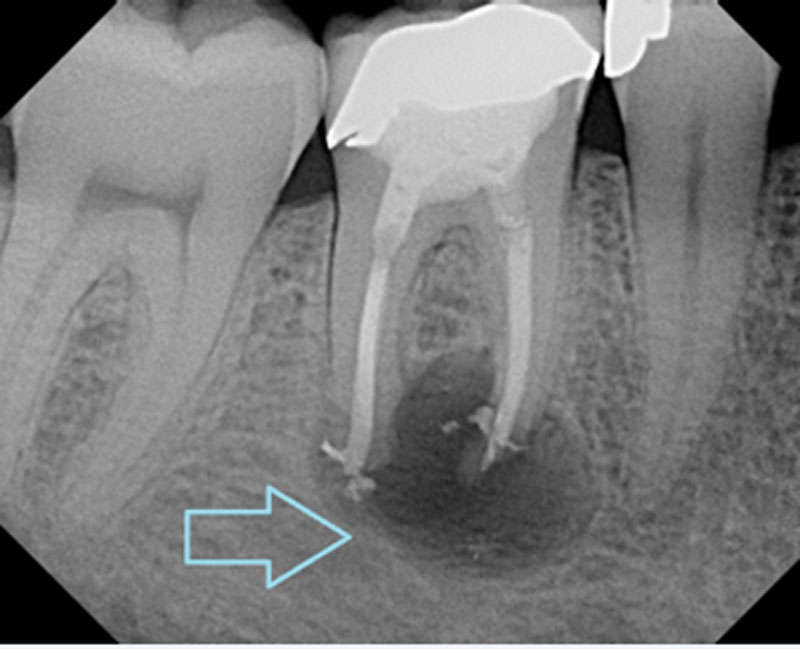

Soms is het verraderlijker: je voelt helemaal niets, maar de tandarts ziet op de röntgenfoto een sluimerende ontsteking.

Precisiewerk: Met een microscoop zoeken we alle verborgen kanaaltjes op. Wat we daar vinden aan 'troep' en bacteriën, halen we weg met minuscule schoonmaakvijltjes.